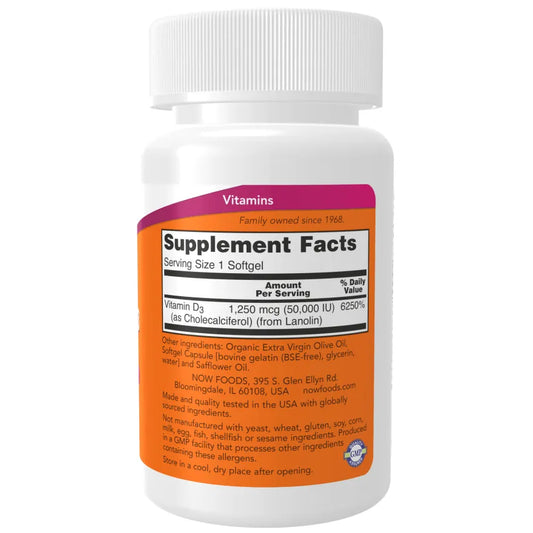

Now - Vitamin D3 50000 IU

Çmimi Lek 1,136.00ÇmimiÇmimi për njësi / perLek 1,420.00Çmimi me ulje Lek 1,136.00Ulje -

NOW -15%

NOW Foods ofron vitamina, minerale, ushqime dhe produkte ushqyese sportive me kosto të efektshme.